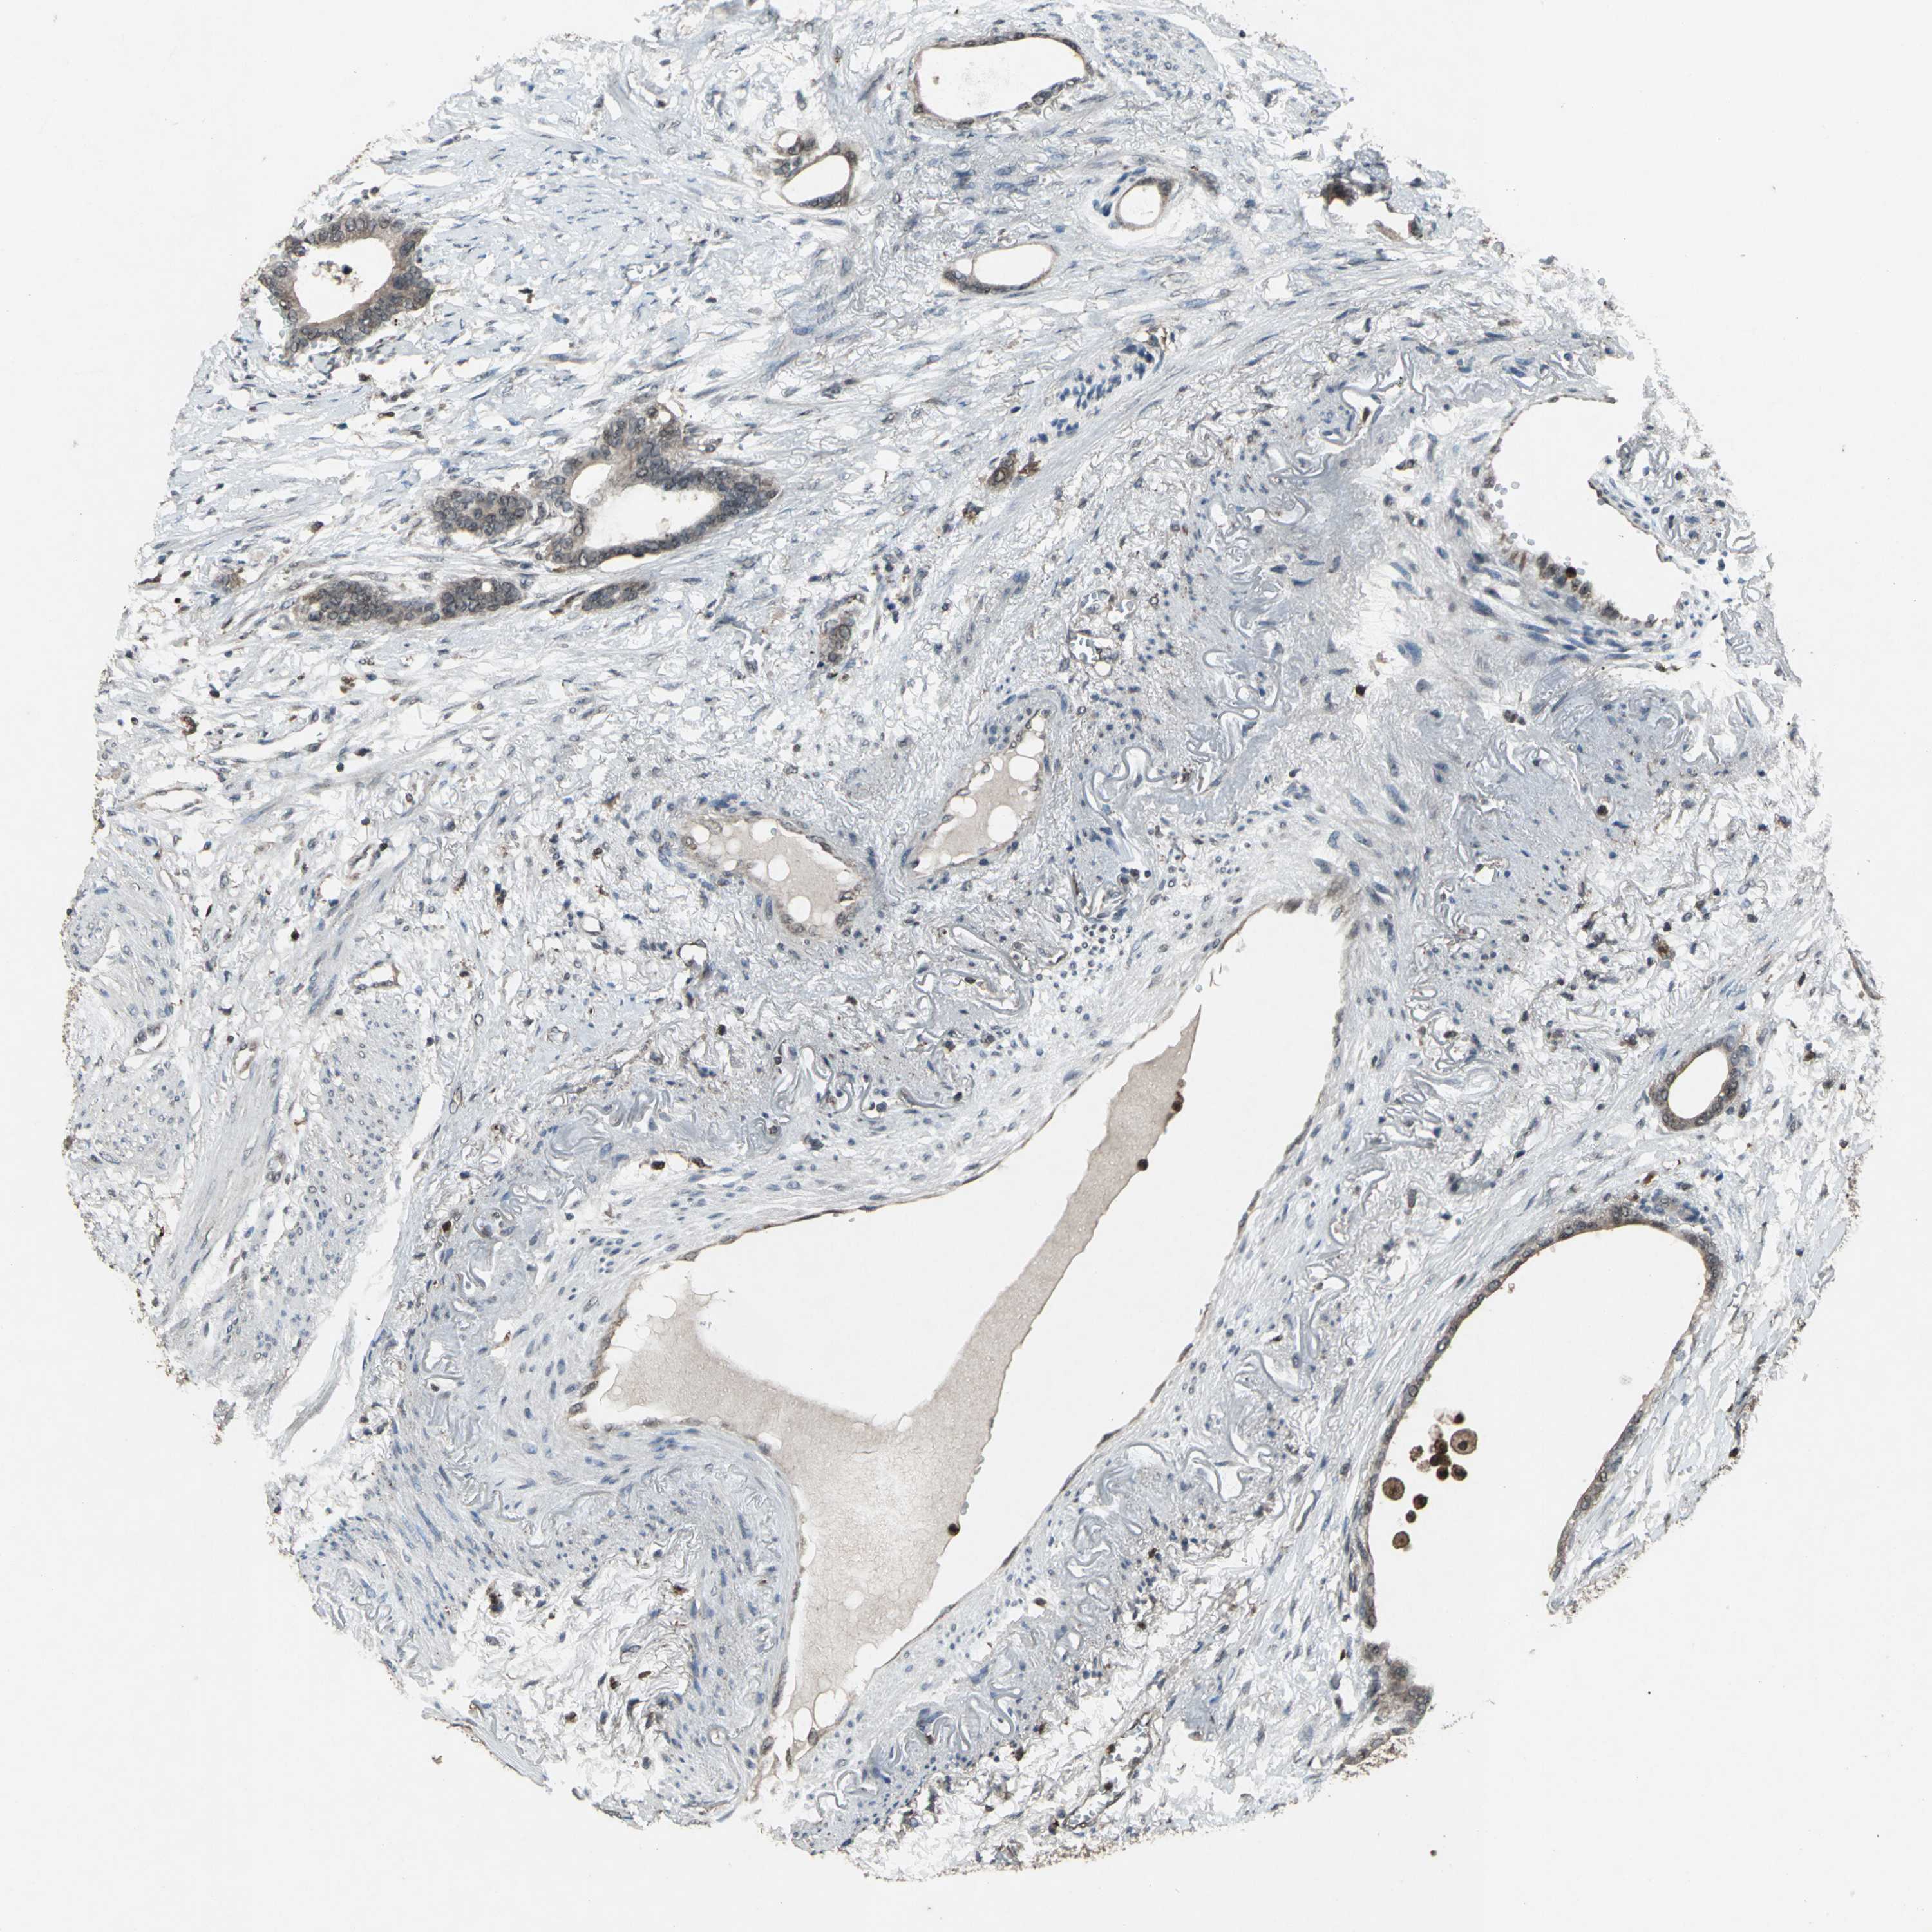

STOMACH CANCER - Protein expressioni

A mouse-over function shows sample information and annotation data. Click on an image to view it in a full screen mode. Samples can be filtered based on level of antibody staining by selecting one or several of the following categories: high, medium, low and not detected. The assay and annotation is described here.

Note that samples used for immunohistochemistry by the Human Protein Atlas do not correspond to samples in the TCGA dataset.

Antibody stainingi

Antibody staining in the annotated cell types in the current human tissue is reported as not detected, low, medium, or high, based on conventional immunohistochemistry profiling in selected tissues. This score is based on the combination of the staining intensity and fraction of stained cells.

Each image is clickable and will lead to virtual microscopy that enables deeper exploration of all samples and also displays staining intensity scores, fraction scores and subcellular localization as well as patient and tissue information for each sample.

Antibody HPA049074

Antibody HPA054496

Antibody CAB006853

Antibody CAB015948

Staining

High

Medium

Low

Not detected

Intensity

Strong

Moderate

Weak

Negative

Quantity

>75%

75%-25%

<25%

None

Location

Nuclear

Cytoplasmic/membranous

Cytoplasmic/membranous,nuclear

Adenocarcinoma, NOS

Adenocarcinoma, High grade